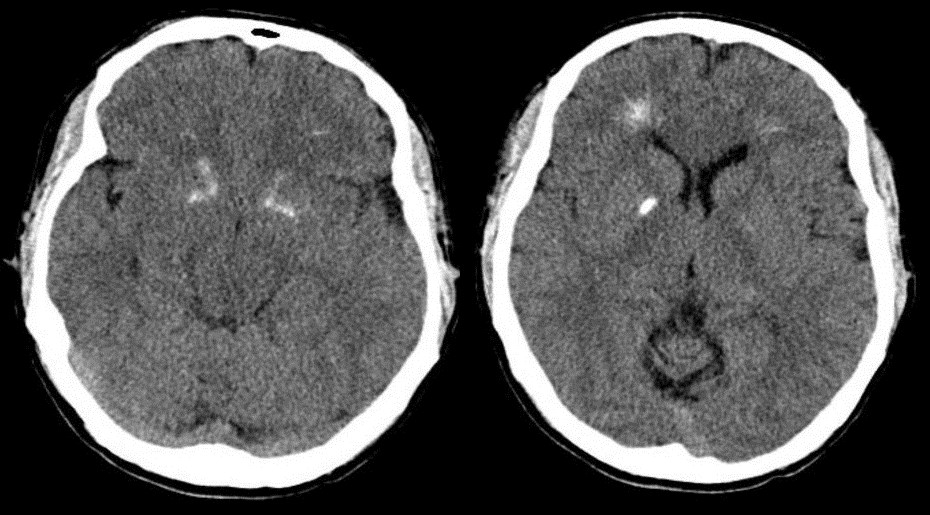

디조지 증후군 환자는 또한 조기 발병 파킨슨병 (PD) 발병 위험이 더 높다. 파킨슨병 진단은 항정신병제 사용으로 인해 최대 10년까지 지연될 수 있는데, 이는 파킨슨 증상을 유발할 수 있기 때문이다.[43][22] 22q11.2 삭제 증후군은 조기 발병 파킨슨병의 위험 증가와 관련이 있다. 관찰되는 신경 병리학은 LRRK2 관련 파킨슨병과 유사하다. 22q11.2 삭제 증후군 환자에게 영향을 미치는 유전자 중 어느 것도 이전에 파킨슨병과 관련이 있었던 적은 없지만, ''DGCR8'', ''SEPT5'', ''COMT'', 그리고 마이크로 RNA miR-185와 같이 가능성이 높은 유전자들이 있다.[43]